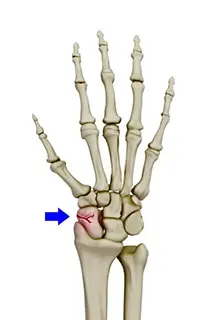

Scaphoid Fracture

Boxer’s Fracture

Wrist Fracture Surgery